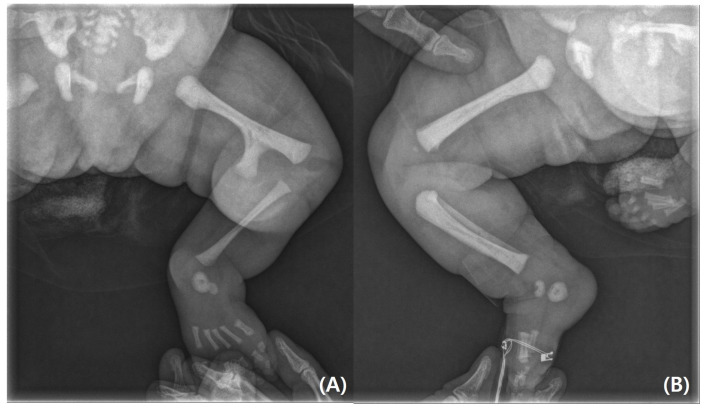

Background: The Gollop-Wolfgang complex is a rare congenital limb deformity characterized by a bifid femur, tibial hemimelia, and ectrodactyly of the hand. First described in 1980, fewer than 200 cases have been reported globally, with an estimated incidence of 1:1,000,000 live births. Case Presentation: We report a 2-month-old female infant with classic features of the Gollop-Wolfgang complex, including a left bifid femur, complete absence of the left tibia, and contralateral tetradactyly. A clinical examination revealed significant limb length discrepancy, knee instability, equinovarus foot deformity, and skeletal abnormalities confirmed by imaging studies. Extensive investigations, including echocardiography and genetic testing, excluded systemic anomalies and identified non-pathogenic variants in the Collagen Type XI Alpha 2 (COL11A2) and EVC2 genes. A surgical resection of the bifid femur was performed. Results: This case highlights the importance of early diagnosis and a multidisciplinary approach in managing the Gollop-Wolfgang complex. While our case presented with typical features, subtle variations highlight the phenotypic spectrum of the condition. The combination of tibial hemimelia and bifid femur frequently necessitates knee disarticulation due to the absence of a viable tibial anlage, while limb salvage techniques remain challenging. A genetic evaluation identified variants of uncertain significance in the COL11A2 and EVC2 genes, indicating that the genetic basis of the condition is not fully understood. Conclusions: These findings emphasize the need for continued genetic research to clarify the etiology of the Gollop-Wolfgang complex and to improve treatment strategies, particularly in refining surgical approaches and exploring new therapeutic options.